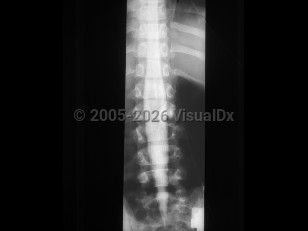

Diastematomyelia, split-cord malformation (SCM), is a rare congenital abnormality in which there is partial or complete cleft in the spinal cord by a sagittal osseous or fibrous septum. It is seen predominantly in females, most often affecting the lower thoracic or upper lumbar segments. Clinically, diastematomyelia often presents as tethered cord syndrome (back pain, abnormal gait, spasticity, bowel / bladder incontinence) in children or young adults, although symptom onset may occur at any age. Patients may have a midline cutaneous abnormality such as a hairy patch or dimple over the affected area. There are two classifications:

- SCM type 1 consists of two hemicords, each with its own dural sheath, separated by a bony or cartilaginous septum.

- SCM type 2 consists of two hemicords within the same dural sheath but separated by a fibrous septum.